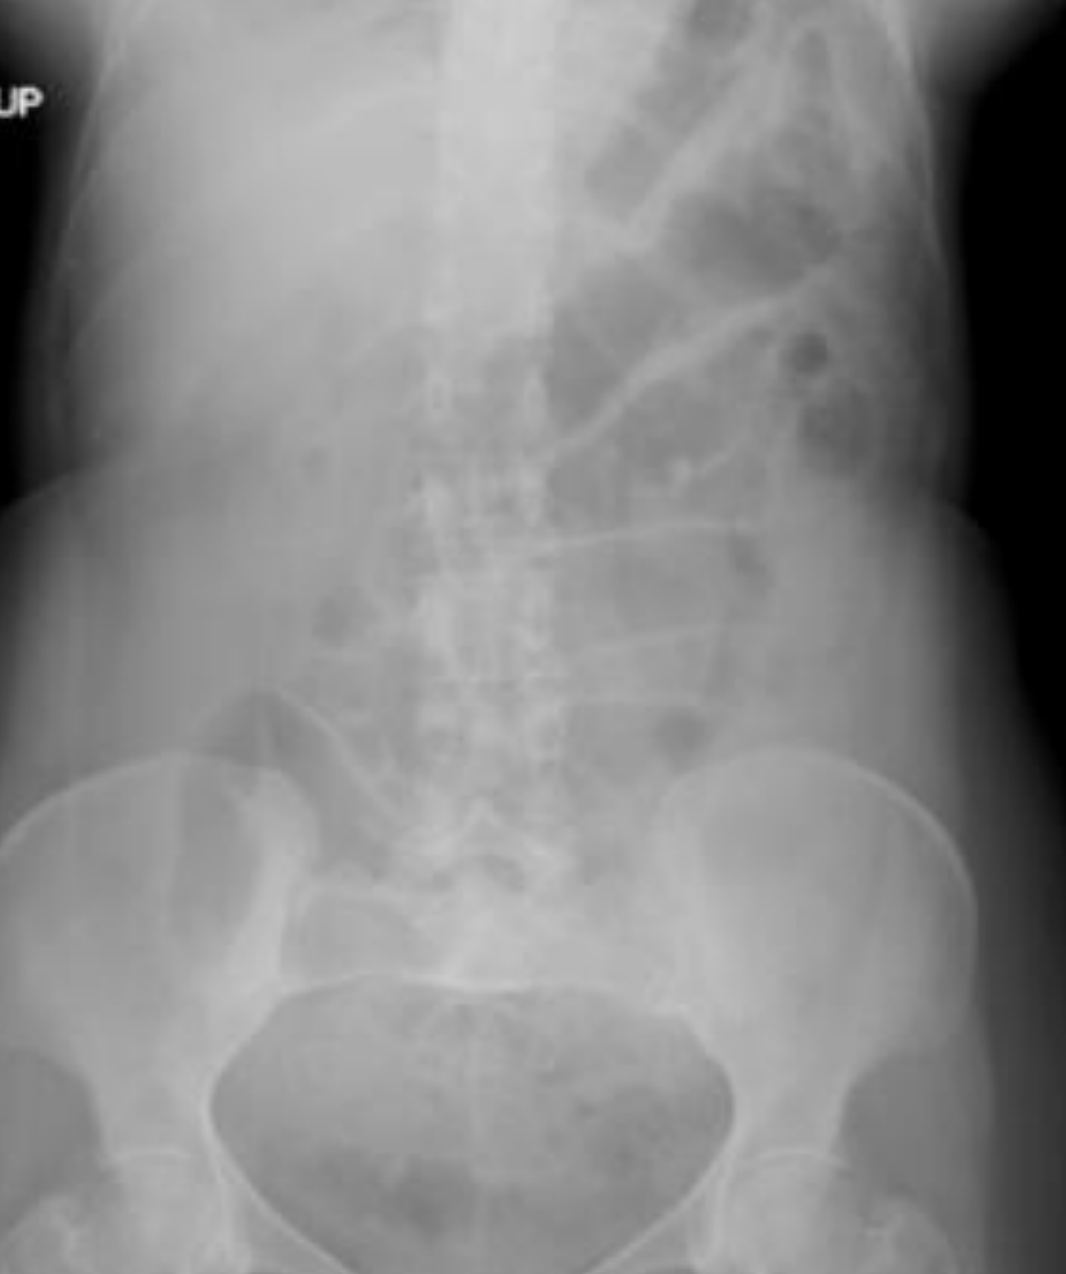

SBO

1. dilated loops of bowel

2. multiple fluid levels

3. small bowel - central/3mm/valvular coneventes